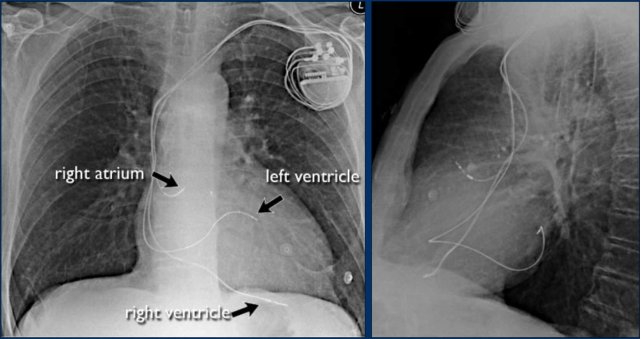

Cardiac Pacemakers

There are various types of cardiac pacing devices, each with specific lead configurations.

In this example:

• Right atrial lead

• Right ventricular lead

• Left ventricular lead via the coronary sinus (used in cardiac resynchronization therapy)

Indication for cardiac resynchronization therapy:

• Patients with ventricular dyssynchrony benefit from biventricular pacing, which improves ventricular coordination and enhances cardiac output.

More on cardiac pacemakers...